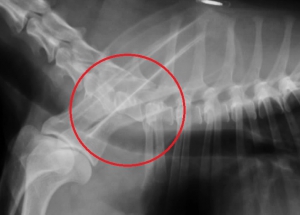

下の写真は日常的に常に頸部の痛みを訴えており、前足の歩行にも問題を生じている患者さんの重度の頸椎~胸椎の変形性脊椎症のレントゲン写真です。

左下の写真、赤丸の中に病変があり、各々の椎骨は両端が大きく変形しております。右下写真は同じ部位の正常なレントゲン写真です。左右の赤丸内の骨の変形が大きいのがお分かりになるかと思います。